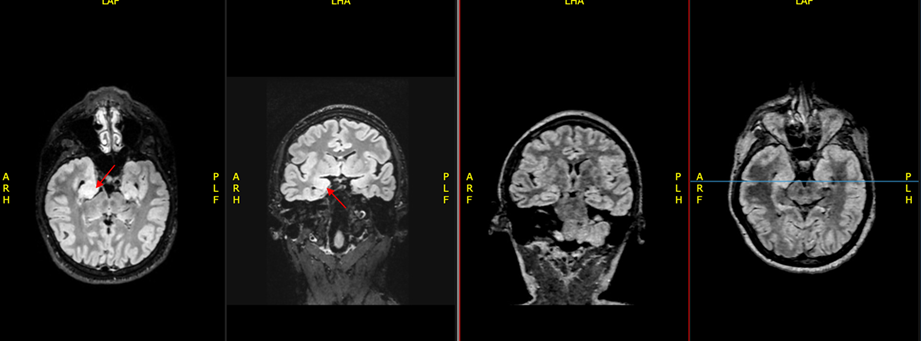

por lo cual requiere intubación orotraqueal y sedación profunda, es llevado a nueva resonancia magnética en protocolo HARNESS de epilepsia. En esta se encuentra que, en comparación con la resonancia realizada el día 16 de mayo, hay una hiperintensidad de los

hipocampos en la secuencia T2, especialmente en el hipocampo derecho. Este hallazgo es compatible con encefalitis autoinmune.

Ilustración 2 A la derecha RM del 25 de mayo, a la izquierda RM del 16 de mayo. Se observa mayor intensidad de los hipocampos en secuencias de información T2 con respecto a la imágen obtenida el 16 de mayo.

Los hallazgos de las neuroimágenes son inespecíficos y pueden incluir áreas de alta señal

en el hipocampo, el cerebelo o los ganglios basales en secuencias ponderadas en T2/FLAIR. El electroencefalograma a menudo es anormal dado por un enlentecimiento generalizado o descargas epileptiformes. Algunos pacientes pueden presentar extreme delta brush, un signo electrográfico muy sensible para esta enfermedad (Schmitt, S. E. et al, 2012).